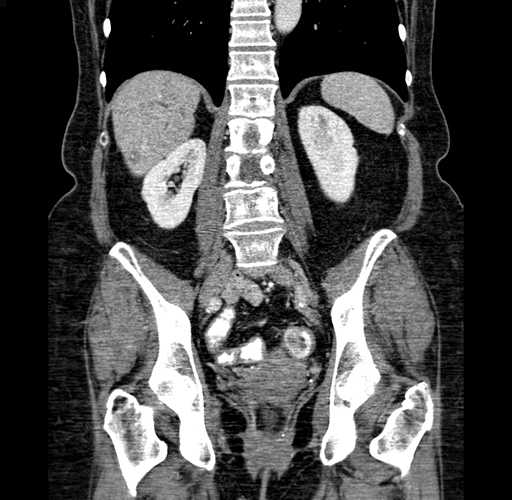

Pre-Chemo: Coronal Venous

Coronal Venous